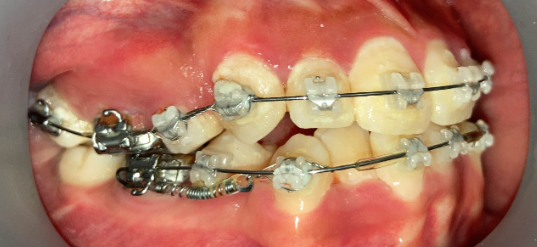

症例:非抜歯+アンカーで改善したケース

症例:ガタガタ+軽度の口元突出 → 非抜歯+アンカーで改善

インプラントアンカー装着中の矯正治療経過|奈良の矯正歯科

アンカー装着中

インプラントアンカーで上の歯列全体を後方に移動。抜歯せずにガタガタと口元の突出感を改善しました。

ℹ️ ただし、この方法には限界があります。歯を後ろに動かせる量には上限があるため、口元の突出が大きい場合やガタガタが重度の場合は、非抜歯では対応できません。適応かどうかは精密検査で判断します。